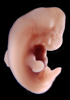

Carnegie Stage 17 (41 post-ovulatory days)

Most embryos at stage 17 are approximately 41 postovulatory days old and measure 11-14 mm in length. Distinguishing criteria for this stage include distinct digital rays in the hand plate, a rounded digital plate in the foot, a complete complement of hillocks on the mandibular and hyoid arches, distinct nasofrontal grooves, and a slight indication of a lumbar curvature.

This specimen does not represent normal development. The caudal nueral tube has failed to close properly.